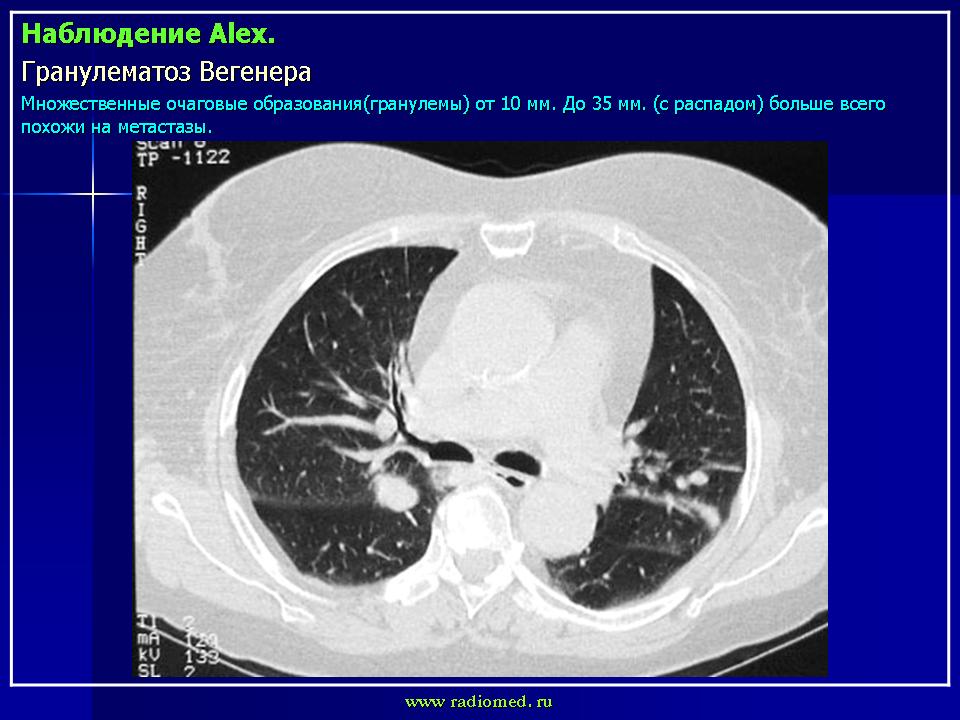

Поражение легкихразвивается у 3/4 больных, проявляется формированием инфильтратов, которые могут распадаться и образовывать полости. Иногда наблюдается плеврит.

Рентгенологическое исследование легких: инфильтраты, часто с распадом и образованием полостей, редко - плеврит.